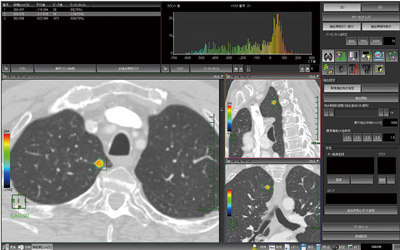

4.肺解析

心臓領域と同様に,呼吸器領域におけるCT検査もさまざまな医療機関で頻繁に行われており,その画像の診断補助ツールとしてワークステーションも多く用いられている。“肺解析”の主な機能は,ユーザーが任意に結節と思われる場所をクリックするだけで,結節部分を抽出することである。また,新たに開発された抽出アルゴリズムで,複雑な形をした結節でも抽出可能であり,容易にそのボリュームを計測できる。設定されたROIにおけるCT値のヒストグラムとそのパーセンタイル値をカラー表示することができ,肺の結節組織の性質を診断することができる。

肺結節の画像診断において,経時的観察は必要不可欠とされており,当社の肺解析の過去検査比較画面は臨床現場での要望を取り入れた画面レイアウト,操作性を持ち,効率良い検査画像の経過観察をサポートする。また,ダブリングタイムを計る機能を有している(図6)。

図6 肺解析画面